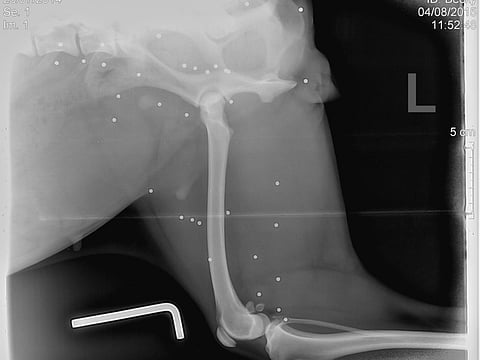

On the third day that Becky was with us, I noticed that she wasn’t walking properly and was very hot. So I took her to the vet where they did x-rays and what we saw then was horrible.

Her x-rays showed that she was drenched with pellets! She was somebody’s pet once and most probably used as a live target, abandoned and left to die. What a cruel life she has experienced. She is only one year old.

The vet said that there is nothing that they could do to remove all the pellets as there are too many and Becky would not survive a long surgery. So she has to live with them. Now I know why she is so scared, does not trust humans, cannot handle any noises and worst of all she has to live with pain, fever and discomfort for the rest of her life.